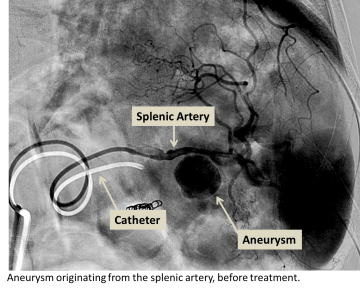

Aneurysm embolization

If the aneurysm is in a suitable location in the body and has specific dimensions, embolization is another treatment that may be considered.

- Aneurysm embolization is also performed by accessing the diseased blood vessel through a needle puncture in the arm or the leg. A wire is navigated into the aneurysmal vessel using a fluroscope (x-ray machine) to guide the navigation.

- Once the vascular tree has been accessed, a catheter is placed over the wire and used to navigate to the aneurysm. Embolization coils are then placed through the catheter into the aneurysm sac filling the sac and slowing blood flow into the sac. Once blood flow within the sac becomes slow enough, the body’s natural clotting cascade causes clot formation within the sac and blood flow within the sac is stopped.

- Contrast may be injected into the vessel to test that the coil pack is properly seated and blood flow into the aneurysm sac is slow enough. Once a satisfactory placement has been made, the wire and catheter is removed from the body and the puncture made in the arm or leg is sealed. The patient is then taken to the recovery area for post-procedural observation.